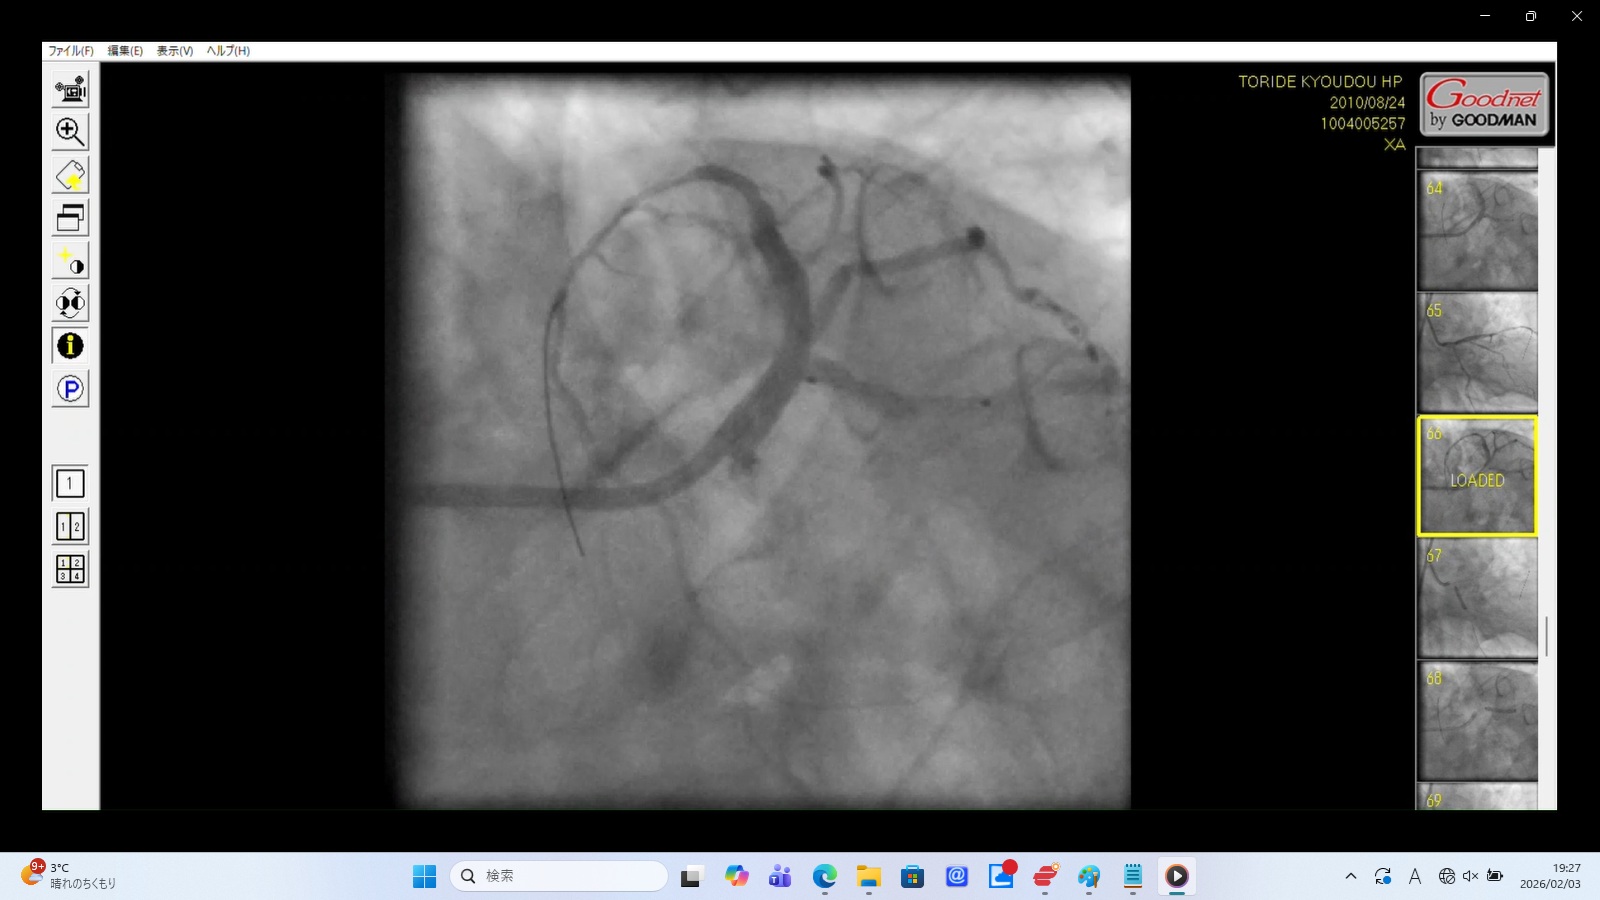

Caption: Iatrogenic Total Occlusion of the Left Main Trunk (LMT)

Medical Findings

Contrast Reflux: Upon injection, the contrast media fails to enter the coronary ostium and instead "bounces back" into the aortic root.

Suspected Dissection: The abrupt cessation of flow at the ostium suggests an iatrogenic dissection or mechanical collapse of the LMT.

Significance: This cuts off blood supply to approximately 75% of the myocardium. This is a periprocedural "Death Sentence" unless immediately bypassed.